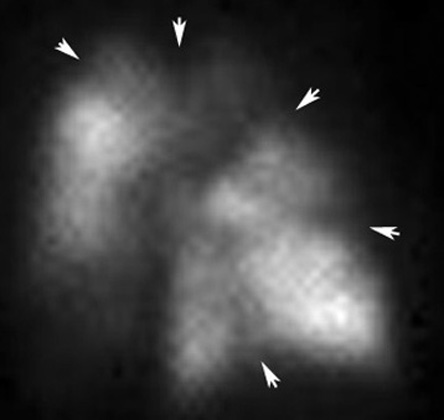

High Probabilty V/Q Scan

There are bilateral segmental perfusion defects. Ventilation lung scan is normal.